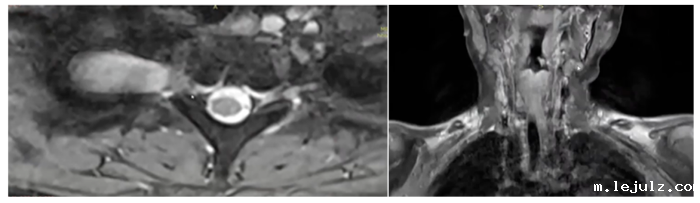

随着年龄增长,轩轩身上的咖啡斑和色素沉着越发明显,潜藏在体内深部的瘤体也明显增大,并且逐渐出现了新发病灶,包括颈部、脊椎旁,骶管、盆腔等。

患儿颈胸段、腰段等多处出现结节